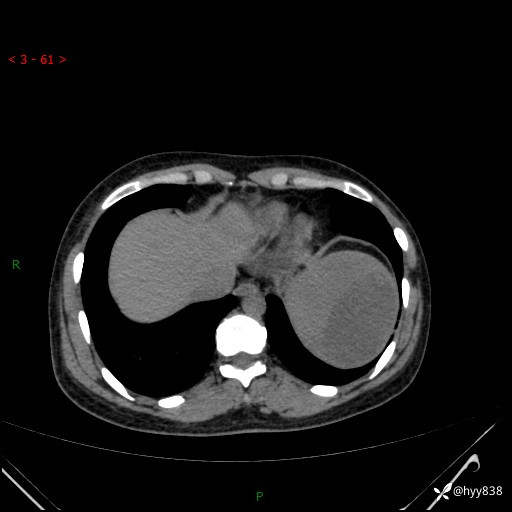

患者性别:男

患者年龄:44岁

主诉:外院超声发现脾脏占位,来我院进一步诊治。

临床诊断:脾脏占位

脾脏CT平扫+增强(动脉期+静脉期)